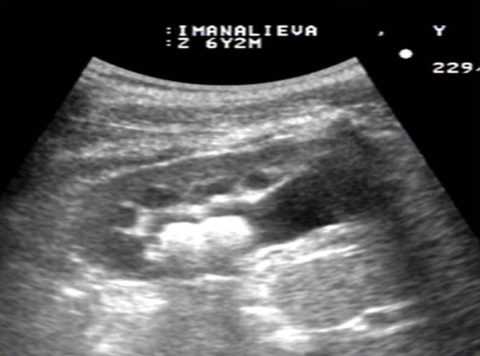

Образование камней в почках связано с нарушением обмена веществ, который позволяет накапливаться в почках нерастворимым солям. Сначала они оседают в виде небольших кристаллов – «песка», и их могут обнаружить на этой стадии при ультразвуковом исследовании.

При поступлении больного на лечение проводят общий анализ мочи, УЗИ и рентген органов мочевыделительной системы, в том числе и внутривенную урографию. При подозрении на камень мочевого пузыря проводится цистоскопия.

- направляется на УЗИ почек, мочевого пузыря и простаты, что поможет быстро и дешево выяснить причину клинических проявлений;